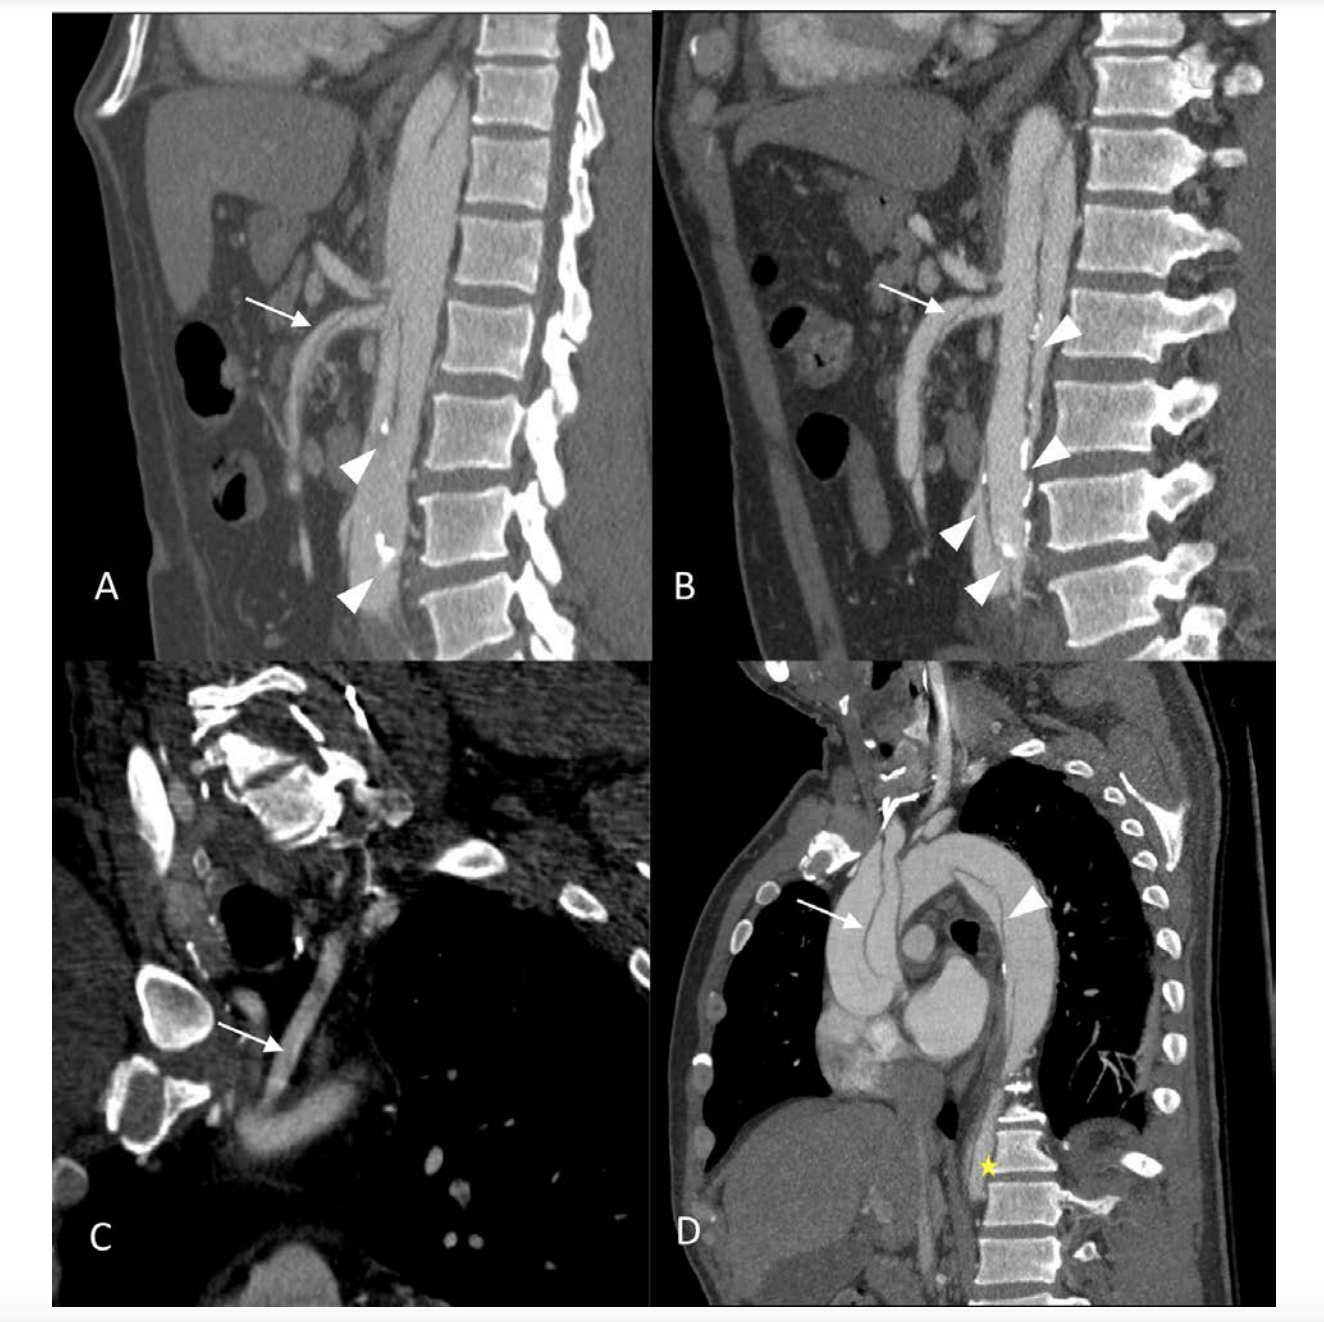

Coronary angiography (CA) was performed 24 hours after admission, an intermediate stenosis was found in the left anterior descending artery (LAD) with TIMI 3 flow (Figure 2). Ventriculography showed mild anteroseptal hypokinesia with a 60% left ventricular ejection fraction (LVEF). Aortic root dilation was observed along with a double contour image suggestive of aortic dissection (Figure 3). Aortic CT was then performed, the study revealed an aortic dissection extending through the thoracic, abdominal and common iliac arteries, classified as a Type A aortic dissection (Figures 4-6). CT angiography 3D reconstruction showed a dissection originating at the aortic root that involved the innominate, left subclavian and left vertebral arteries as well as the descending aorta and extended through the entire course of the common iliac artery causing left iliac artery occlusion (Figure 7).